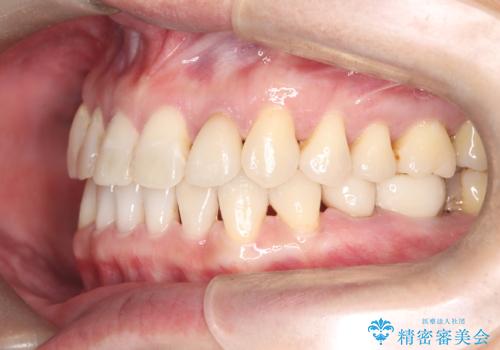

治療は、まずインビザラインを使用して全体の隙間を閉じつつ、将来インプラントを入れるためのスペースをミリ単位で精密に調整しました。マウスピース矯正は、歯の移動量をデジタルで管理できるため、最終的な被せ物の大きさに合わせた理想的な位置取りが可能です。

矯正によって土台となる歯列が整った段階で、欠損部位へインプラントを埋入しました。これにより、周囲の歯を削ることなく、天然歯のような噛み心地を再現することができました。

矯正とインプラントを組み合わせたことで、見た目のコンプレックスが解消されただけでなく、全体の噛み合わせも安定しました。隙間がなくなったことで発音や清掃性も向上し、長期的に健康を維持できる口腔環境が整いました。